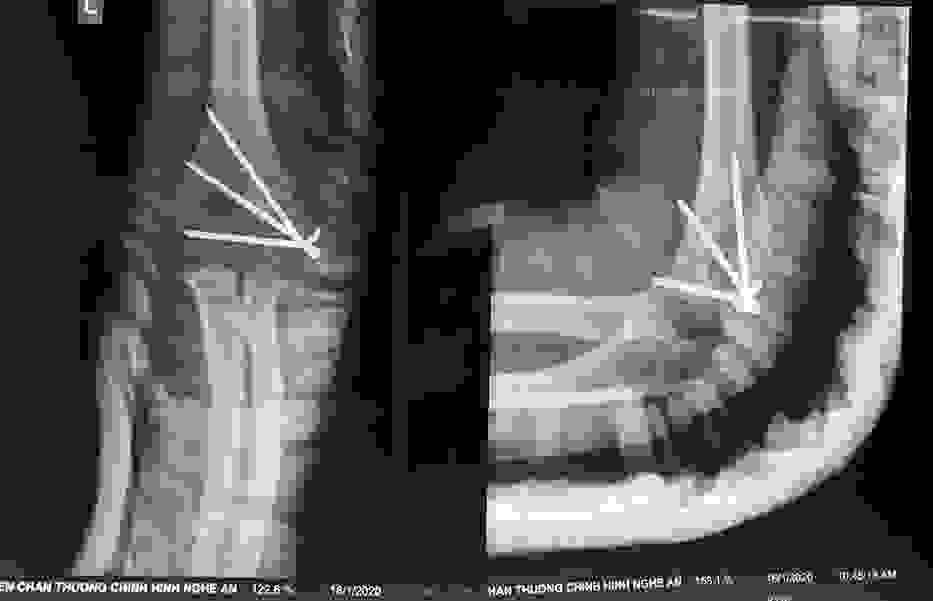

Phẫu thuật thành công ca bệnh hiếm gặp...khớp giả bẩm sinh xương chày

26/06/2019 17:00

Đã xem: 3184

Bệnh viện Chấn thương- Chỉnh hình Nghệ An, vừa phẫu thuật thành công cho bệnh nhi khớp giả bẩm sinh xương chày